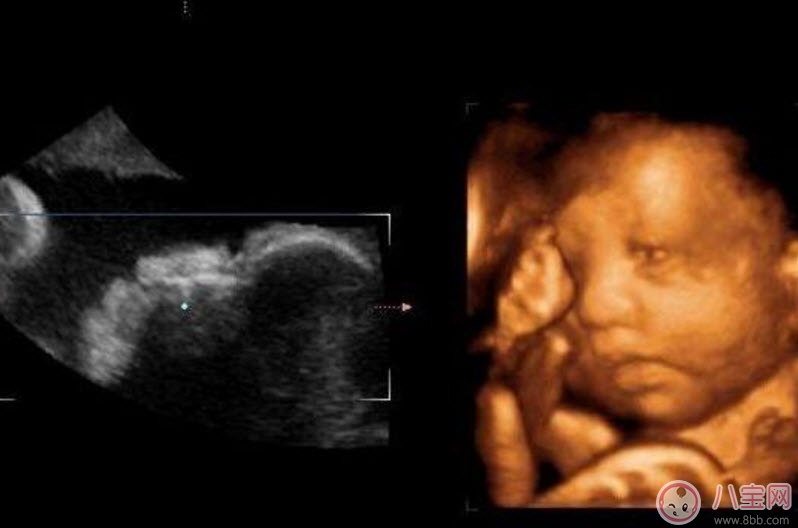

四維彩超的全稱是四維彩色超聲診斷儀,是世界上最先進(jìn)的彩色超聲設(shè)備。四維彩超能夠表面成像,可以更佳清晰的查出來(lái)胎兒的四肢發(fā)育是否畸形,腦膜膨出,是否唇腭裂、脊柱裂等先天畸形,及早發(fā)現(xiàn)及早的做出解決方案。

三維、四維超聲就是把很多個(gè)二維斷面圖像通過(guò)計(jì)算機(jī)重建成一個(gè)立體的圖像。相當(dāng)于把切成很多片的西瓜,重新堆疊成一個(gè)完整的西瓜,這個(gè)堆疊過(guò)程由計(jì)算機(jī)完成。三維、四維的區(qū)別在于,三維是照片,四維是影片,四維就是會(huì)動(dòng)的三維照片(實(shí)時(shí)三維)。